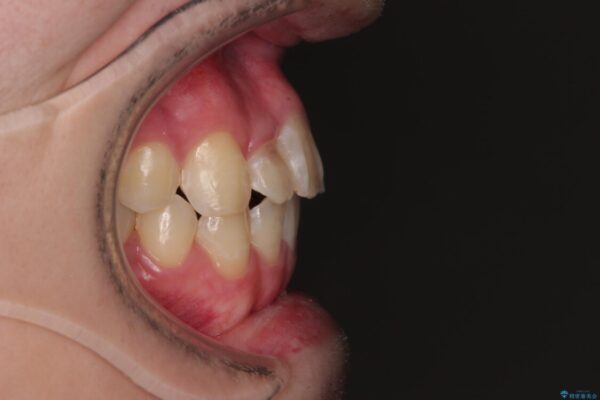

治療後

• 1年でここまで変わる!歯列のがたつきと正中のズレを改善した矯正治療(メタルブラケット×MARPE) 治療後画像

適切な診断と装置の選択により、1年という短期間でここまで改善できます。

見た目の美しさだけでなく、将来のむし歯や歯周病リスクを減らすことにもつながる治療です。